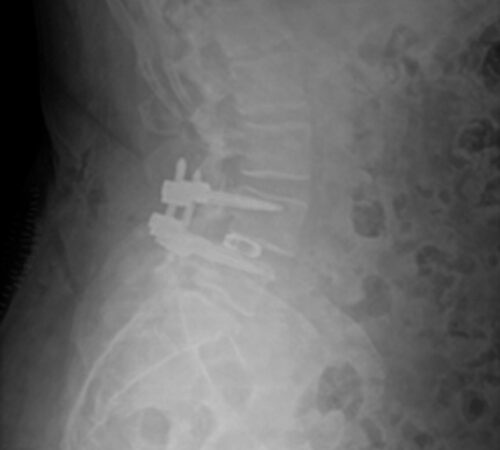

DIAGNOSI:

SPONDILOLISTESI CON STENOINSTABILITA’ L3-L5

Radiografia lombare pre-operatoria

Intervento chirurgico eseguito:

Artrodesi lombare mediante viti transpeducolari L3-L4-L5 + introduzione di cage intersomatica plif

Radiografia post-operatoria